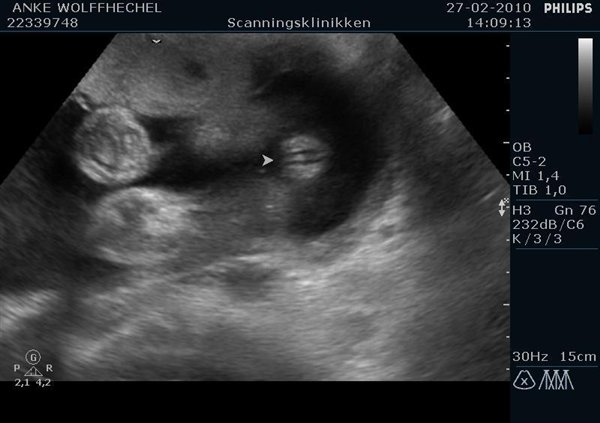

Så fik vi endelig kønnet at vide!! Og jeg kan love for, det blev vist frem..

Jeg har vedlagt et par billeder, et af kønnet i 2d, og nogle af vores fine pige med den søde knoldenæse og de store kinder. (Næsen er i øvrigt ikke så stor i virkeligheden, den ser kun sådan ud, fordi den optages lige forfra

)